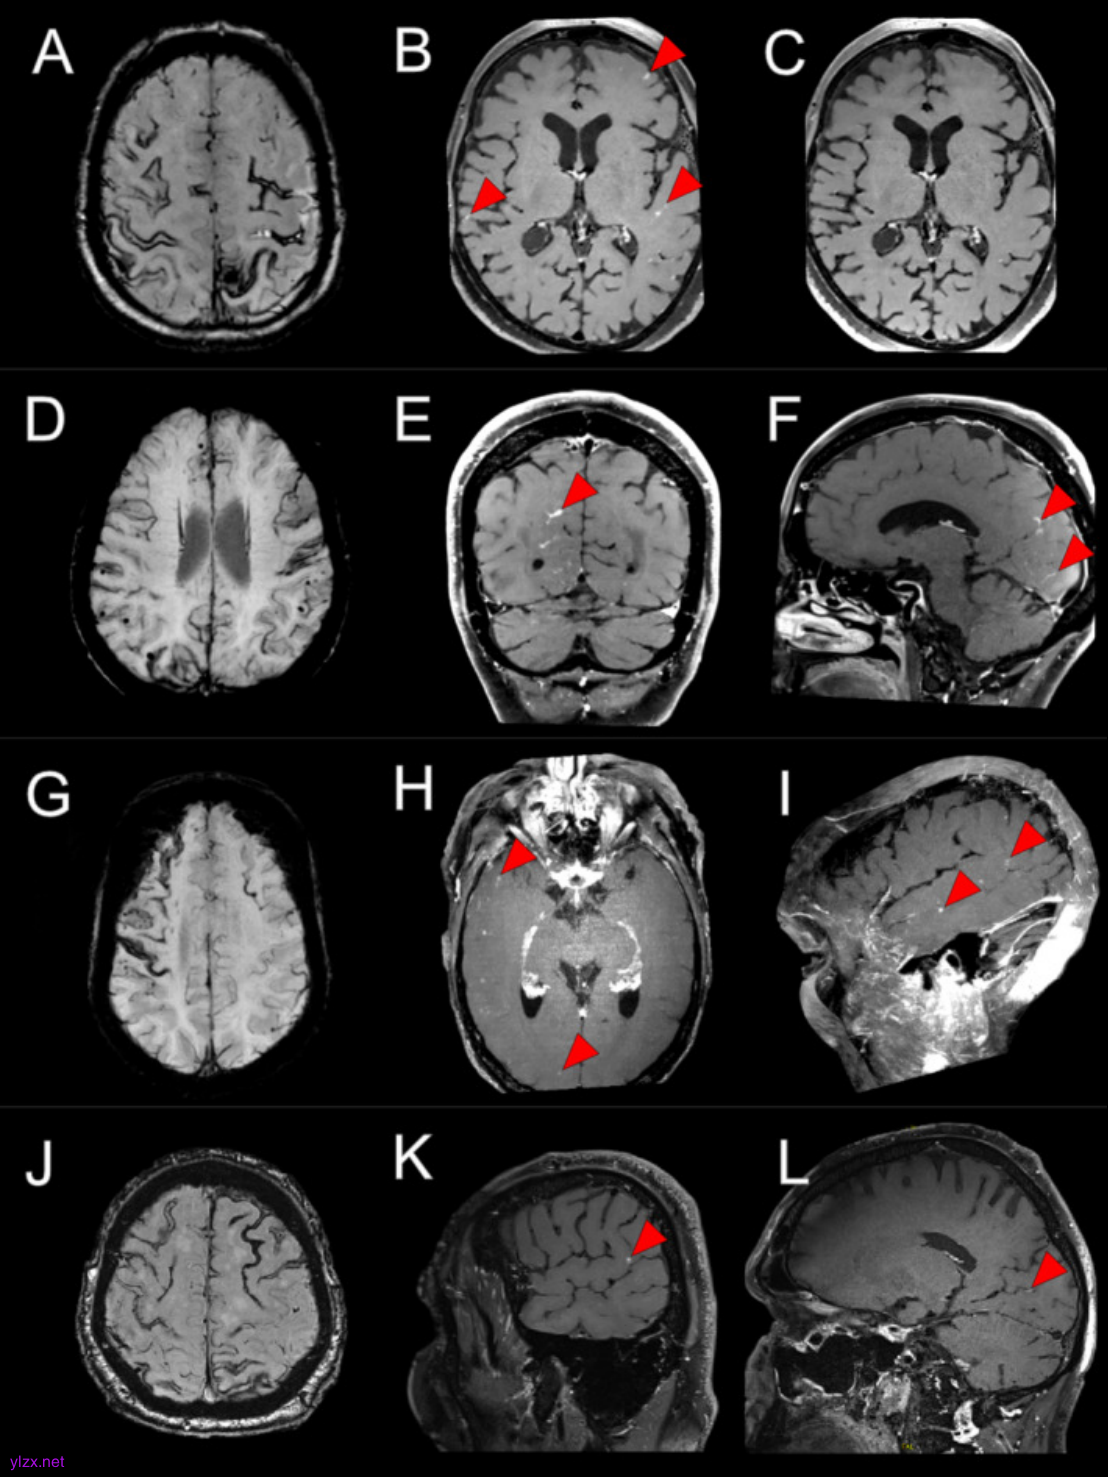

图2.每行包含案例 5 和 6 的磁共振成像

使用 VWI 的高分辨率造影剂后 MRI,在 6 名持续性 CAA 相关 TFNE 患者中描述了软脑膜、实质和小皮质动脉壁增强的各种组合,与短暂性炎症一致。在 6 例病例中的 5 例中,增强包括与解剖学上与 TFNE 症状相关的区域,尽管增强通常相当弥漫,以后(顶枕)为主。这些观察结果表明,炎症可能在持续性 CAA 相关 TFNE 的病理生理学中发挥作用,并且可能在更普遍的 CAA 中发挥作用。

钆造影剂后脑部 MRI 和高分辨率血管壁成像 (vessel wall imaging,VWI) 提供了一种非侵入性方法来评估单个小血管内的血脑屏障 (blood–brain barrier,BBB) 破坏和血管病变变化。1月8日,伦敦大学 David J Werring教授团队在Annals of Neurology(IF=8.1)在线发表了题为“Inflammation in Cerebral Amyloid Angiopathy-Related Transient Focal Neurological Episodes”的研究,描述了 6 名持续性 CAA 相关 TFNE 患者,其中钆后 MRI 发现与小血管、软脑膜和脑实质急性炎症一致的异常。